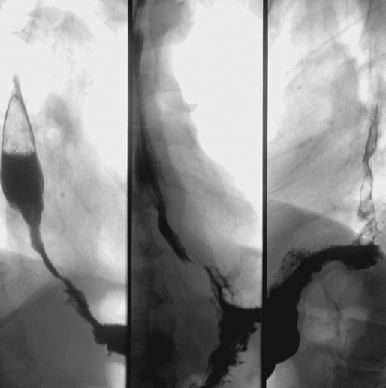

Для исследования характера опухолевой инфильтрации по желудку всем больным выполняются ;рентгенологическое и эндоскопическое ;исследования. ;Только комбинация обоих методов позволяет оценить характер опухолевой инфильтрации по желудку с возможным переходом на смежные структуры ЖКТ по протяжению (пищевод, двенадцатиперстная кишка) и классифицировать тип опухолевого роста, что является интегральным показателем, объединяющим данные рентгенологического и эндоскопического обследования.

Рентгенологическое исследование ;является основным при определении локализации и протяженности поражения стенки желудка. В процессе рутинного рентгенологического исследования желудка, независимо от локализации первичной опухоли, чрезвычайно важно тщательное исследование всех отделов органа в связи с возможным мультицентрическим характером роста или наличием интрамуральных метастазов.

Согласно классификации ЯАРЖ 1998 г., орган разделяется на 3 отдела: ;верхнюю, среднюю и нижнюю ;трети. Детальное разделение желудка на отделы помимо четкого представления об уровне поражения позволяет хирургу оценить топографо-анатомические взаимоотношения и возможные варианты опухолевой инвазии в окружающие структуры, а также до операции характеризовать основное направление лимфогенного метастазирования, что является немаловажным при планировании дальнейшего обследования и хирургического лечения.

Рентгенологическое обследование целесообразно проводить комплексно, используя ;тугое заполнение и двойное контрастирование. Первый метод наиболее информативен при экзофитных опухолях, второй (включающий сочетанное применение ;бария с шипучими субстанциями ;на фоне релаксации стенки желудка с применением ;глюкагона) — позволяет оценить интрамуральную инфильтрацию желудочной стенки и вовлечение смежных структур (пищевод, двенадцатиперстная кишка) на протяжении. Основным преимуществом метода двойного контрастирования является возможность детального изучения минимальных изменений слизистой (за счет расправления желудка газом), а также — тщательного изучения проксимального отдела желудка, что невозможно при применении лишь тугого заполнения.

Следует отметить, что ;все больные с выявленными при рентгенологическом исследовании язвами желудка должны обязательно дополнительно проходить эндоскопическое исследование с морфологической верификацией изменений слизистой в области язвы. Суждение о характере язвы лишь на основании данных рентгенологического исследования не может на сегодняшний день рассматриваться как достоверное.